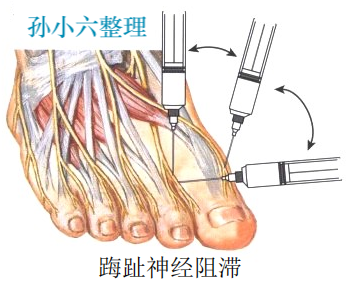

手术治疗

手术方法